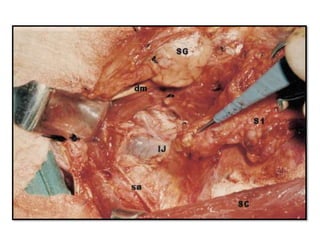

• #87 Surgical field prepared for the dissection of the spinal accessory area on the right side of the neck. SC, Sternocleidomastoid muscle; IJ, Internal jugular vein; sa, spinal accessory nerve; hn, hypoglossal nerve; mn, marginal mandibular branch of the facial nerve; fv, facial vein; SG, submandibular gland; pg, tail of the parotid gland; F, fascia dissected form the upper part of the surgical field. To approach this area the sternocleidomastoid muscle is retracted posteriorly, and the posterior belly of the digastric muscle is pulled superiorly with a smooth blade retractor (Fig. 4-26). The wet surgical sponges previously left over the nerve at the level of its entrance in the sternocleidomastoid muscle are removed and the nerve is dissected toward the carotid sheath.

• #95 The fibrofatty tissue lying posterior and superior to the nerve is passed under the nerve. sa, spinal accessory nerve; IJ, internal jugular vein; SG, submandibular gland; dm, digastric muscle; SC, sternocleidomastoid muscle; ls, levator scapulae muscle; S1, specimen from the submandibular and upper jugular area; S2, specimen from the upper spinal accessory and posterosuperior jugular area.